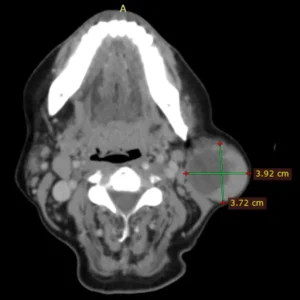

Patología de glándulas salivales

Evaluación de bultos, inflamación o dolor en las glándulas que producen saliva, como parótidas o submandibulares.

Tumores Óseos